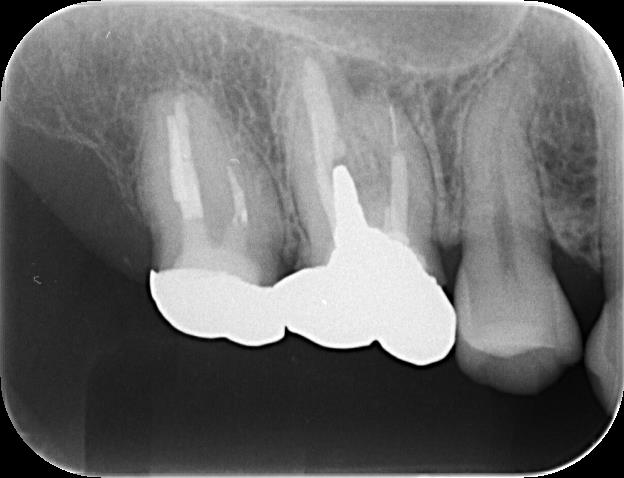

下の写真は、根尖病巣(根の周囲に膿が溜まる病気)による痛みを訴え、根管治療を行った方です。

初診時のレントゲン写真を見ると、左から2番目の歯の病巣がある歯根の先端に、金属片と思われる像が認められました。

マイクロスコープを使用しながら根管の充填材を除去していくと、やはり金属片が存在していました。

根管の奥の方に光っているものがそうです。

裸眼やルーペでは、通常ここまで見ることはできません。

マイクロスコープで覗きながら、超音波機器などを使用して歯と金属片の間に振動を与え、うまく除去することができました。